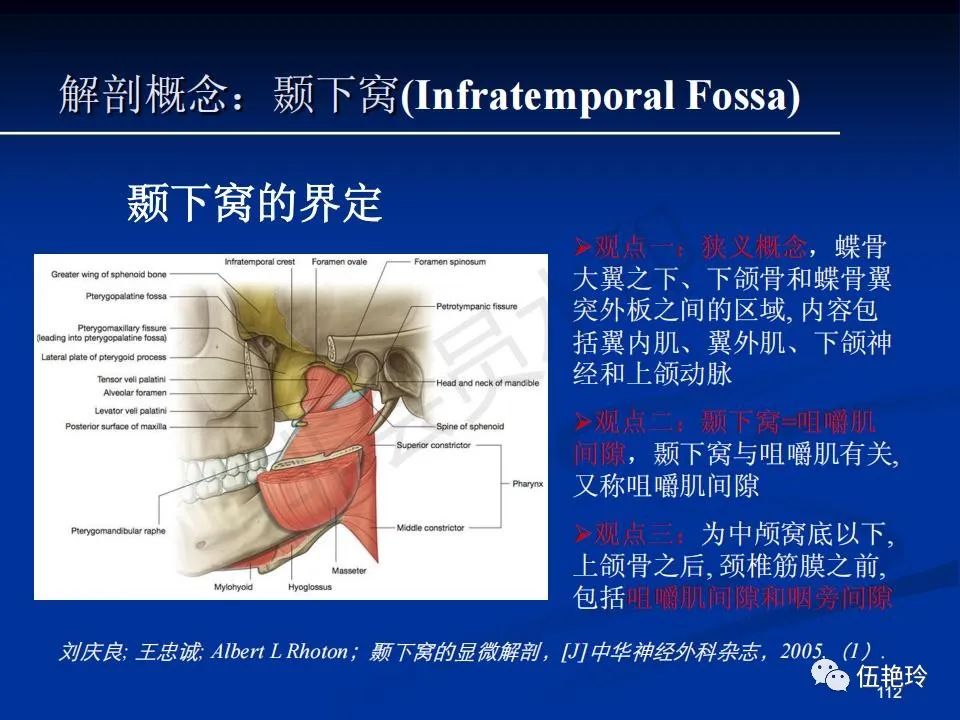

颞下窝与咀嚼肌间隙

2.31 向上颅内:①鼻咽顶壁→破裂孔(岩尖、斜坡)→蝶窦、海绵窦;②鼻咽顶壁→蝶骨基底部→蝶窦、海绵窦;③鼻咽侧壁→茎突前间隙→蝶骨大翼(卵圆孔)→海绵窦;④鼻咽侧壁→茎突前间隙→翼腭窝→ 颞下窝;⑤鼻咽前壁→鼻腔→翼突、翼腭窝→眶下裂→眶尖→海绵窦;⑥鼻咽前壁→鼻腔→上颌窦、筛窦;